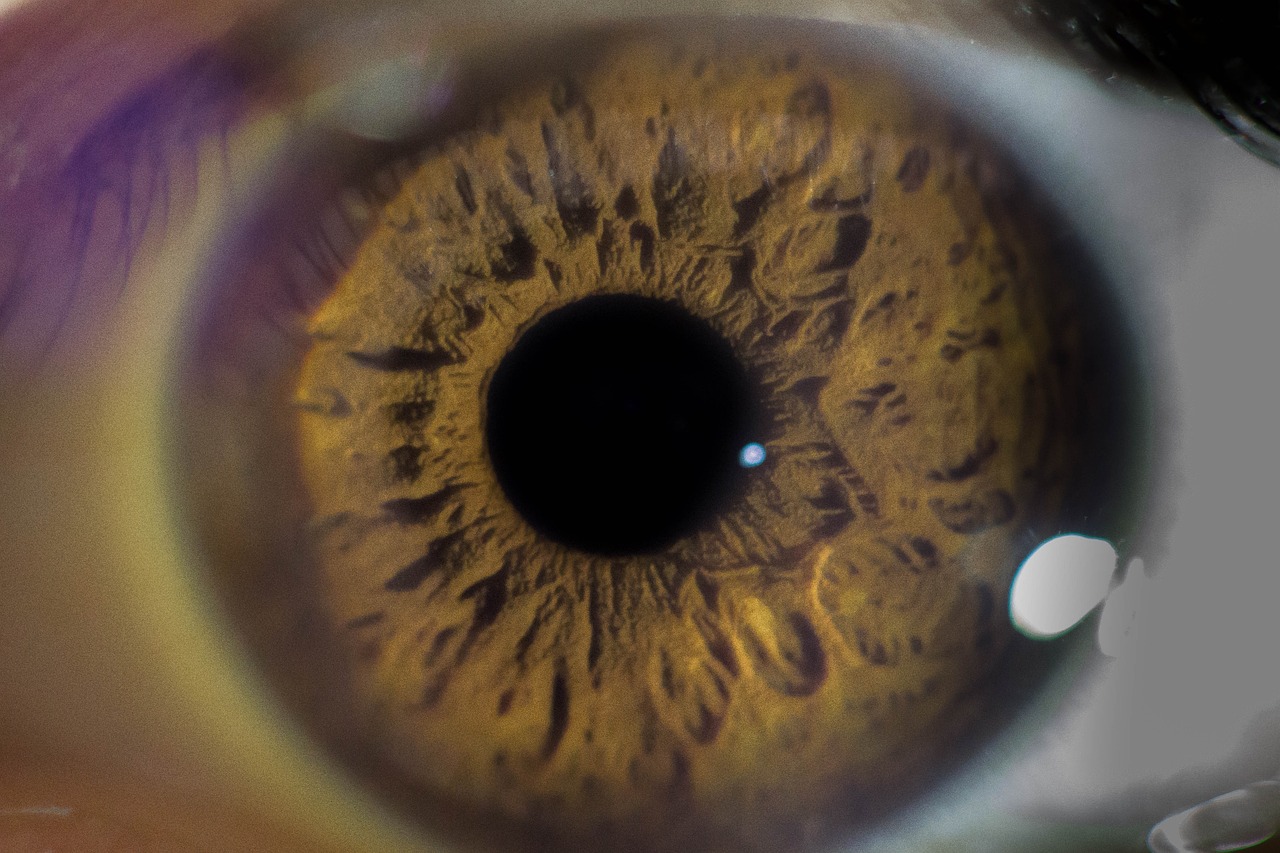

Ερευνητές στην Αυστραλία αναπτύσσουν μικροσκοπικά φωτοβολταϊκά τα οποία τοποθετούνται στον αμφιβληστροειδή του ματιού με σκοπό την αποκατάσταση της όρασης και τη βελτίωση της ποιότητας ζωής των ατόμων που πάσχουν από ανίατες οφθαλμικές παθήσεις.

Τώρα, ερευνητές από το Πανεπιστήμιο της Νέας Νότιας Ουαλίας (UNSW) διερευνούν εάν μια παρόμοια νευροπροσθετική τεχνολογία μπορεί να αποκαταστήσει την όραση σε άτομα με κατεστραμμένους φωτοϋποδοχείς, εξειδικευμένα κύτταρα στον αμφιβληστροειδή ικανά να απορροφούν φως και να το μετατρέπουν σε ηλεκτρικά σήματα που μπορούν να σταλούν στον οπτικό φλοιό.